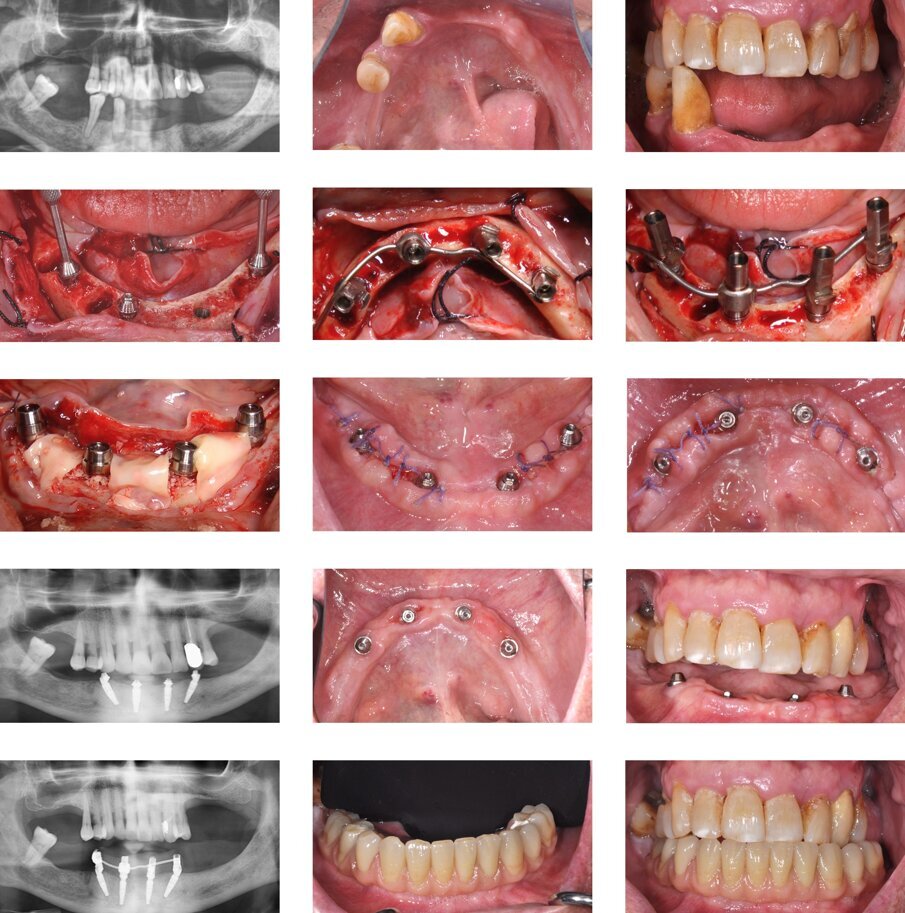

Fig. 3 - Un caso illustrativo dell’impiego della tecnica OkSplint. Un paziente, con alcuni elementi compromessi nell’arcata inferiore, viene sottoposto ad estrazione e riabilitazione dell’arcata ora edentula attraverso l’inserimento di quattro impianti osteointegrati, secondo l’approccio “All-on-four”. Gli abutment sono splintati attraverso la tecnica OkSplint per realizzare una protesi tipo Toronto-Branemark.